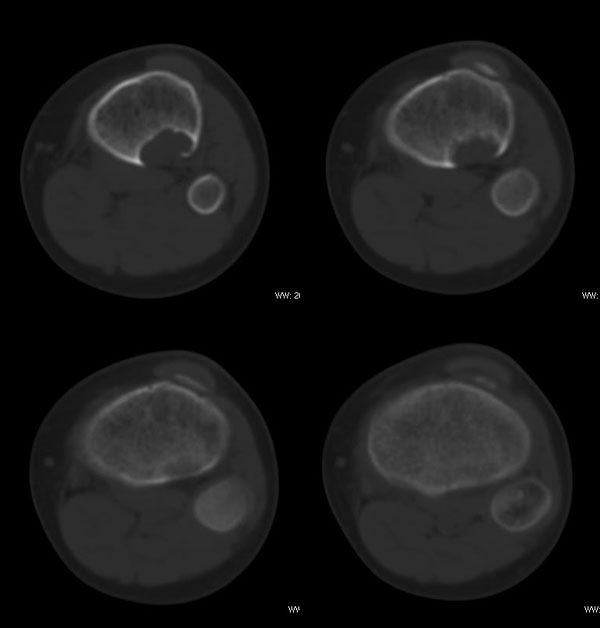

以下是引用37度在2010-1-7 12:22:00的发言:[br]左胫骨上段纤维性骨皮质缺损(非骨化性纤维瘤).

以下是引用dyqct在2010-1-7 14:54:00的发言:[br]考虑为左胫骨上段纤维性骨皮质缺损 ,可自愈.

以下是引用xkncyyhyq在2010-1-7 9:54:00的发言:[br]考虑为纤维性骨皮质缺损